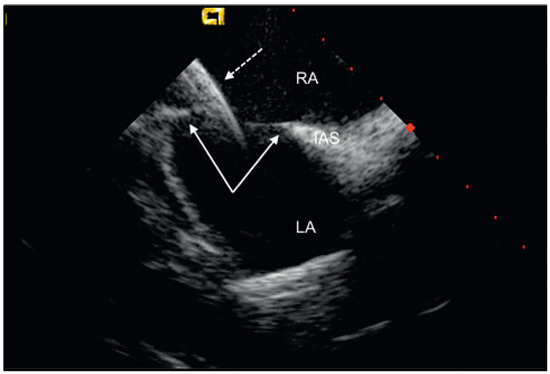

Percutaneous Implantation of an ASD Occluder with Intracardiac Ultrasound

by Frank Enseleit, Oliver Kretschmar and Thomas F. Lüscher

Cardiovasc. Med. 2010, 13(9), 290; https://doi.org/10.4414/cvm.2010.01522 - 15 Sep 2010

A 52-year-old female was admitted for further evaluation of a continuous heart murmur. Transthoracic echocardiography revealed a secundum type atrial septal defect (ASD II) with a size of 13 × 16 mm and considerable left-to-right shunt (Qp/Qs = 2), as well as elevated [...] Read more.

A 52-year-old female was admitted for further evaluation of a continuous heart murmur. Transthoracic echocardiography revealed a secundum type atrial septal defect (ASD II) with a size of 13 × 16 mm and considerable left-to-right shunt (Qp/Qs = 2), as well as elevated pulmonary artery pressure (RV/RA pressure gradient = 38 mm Hg) [...] Full article